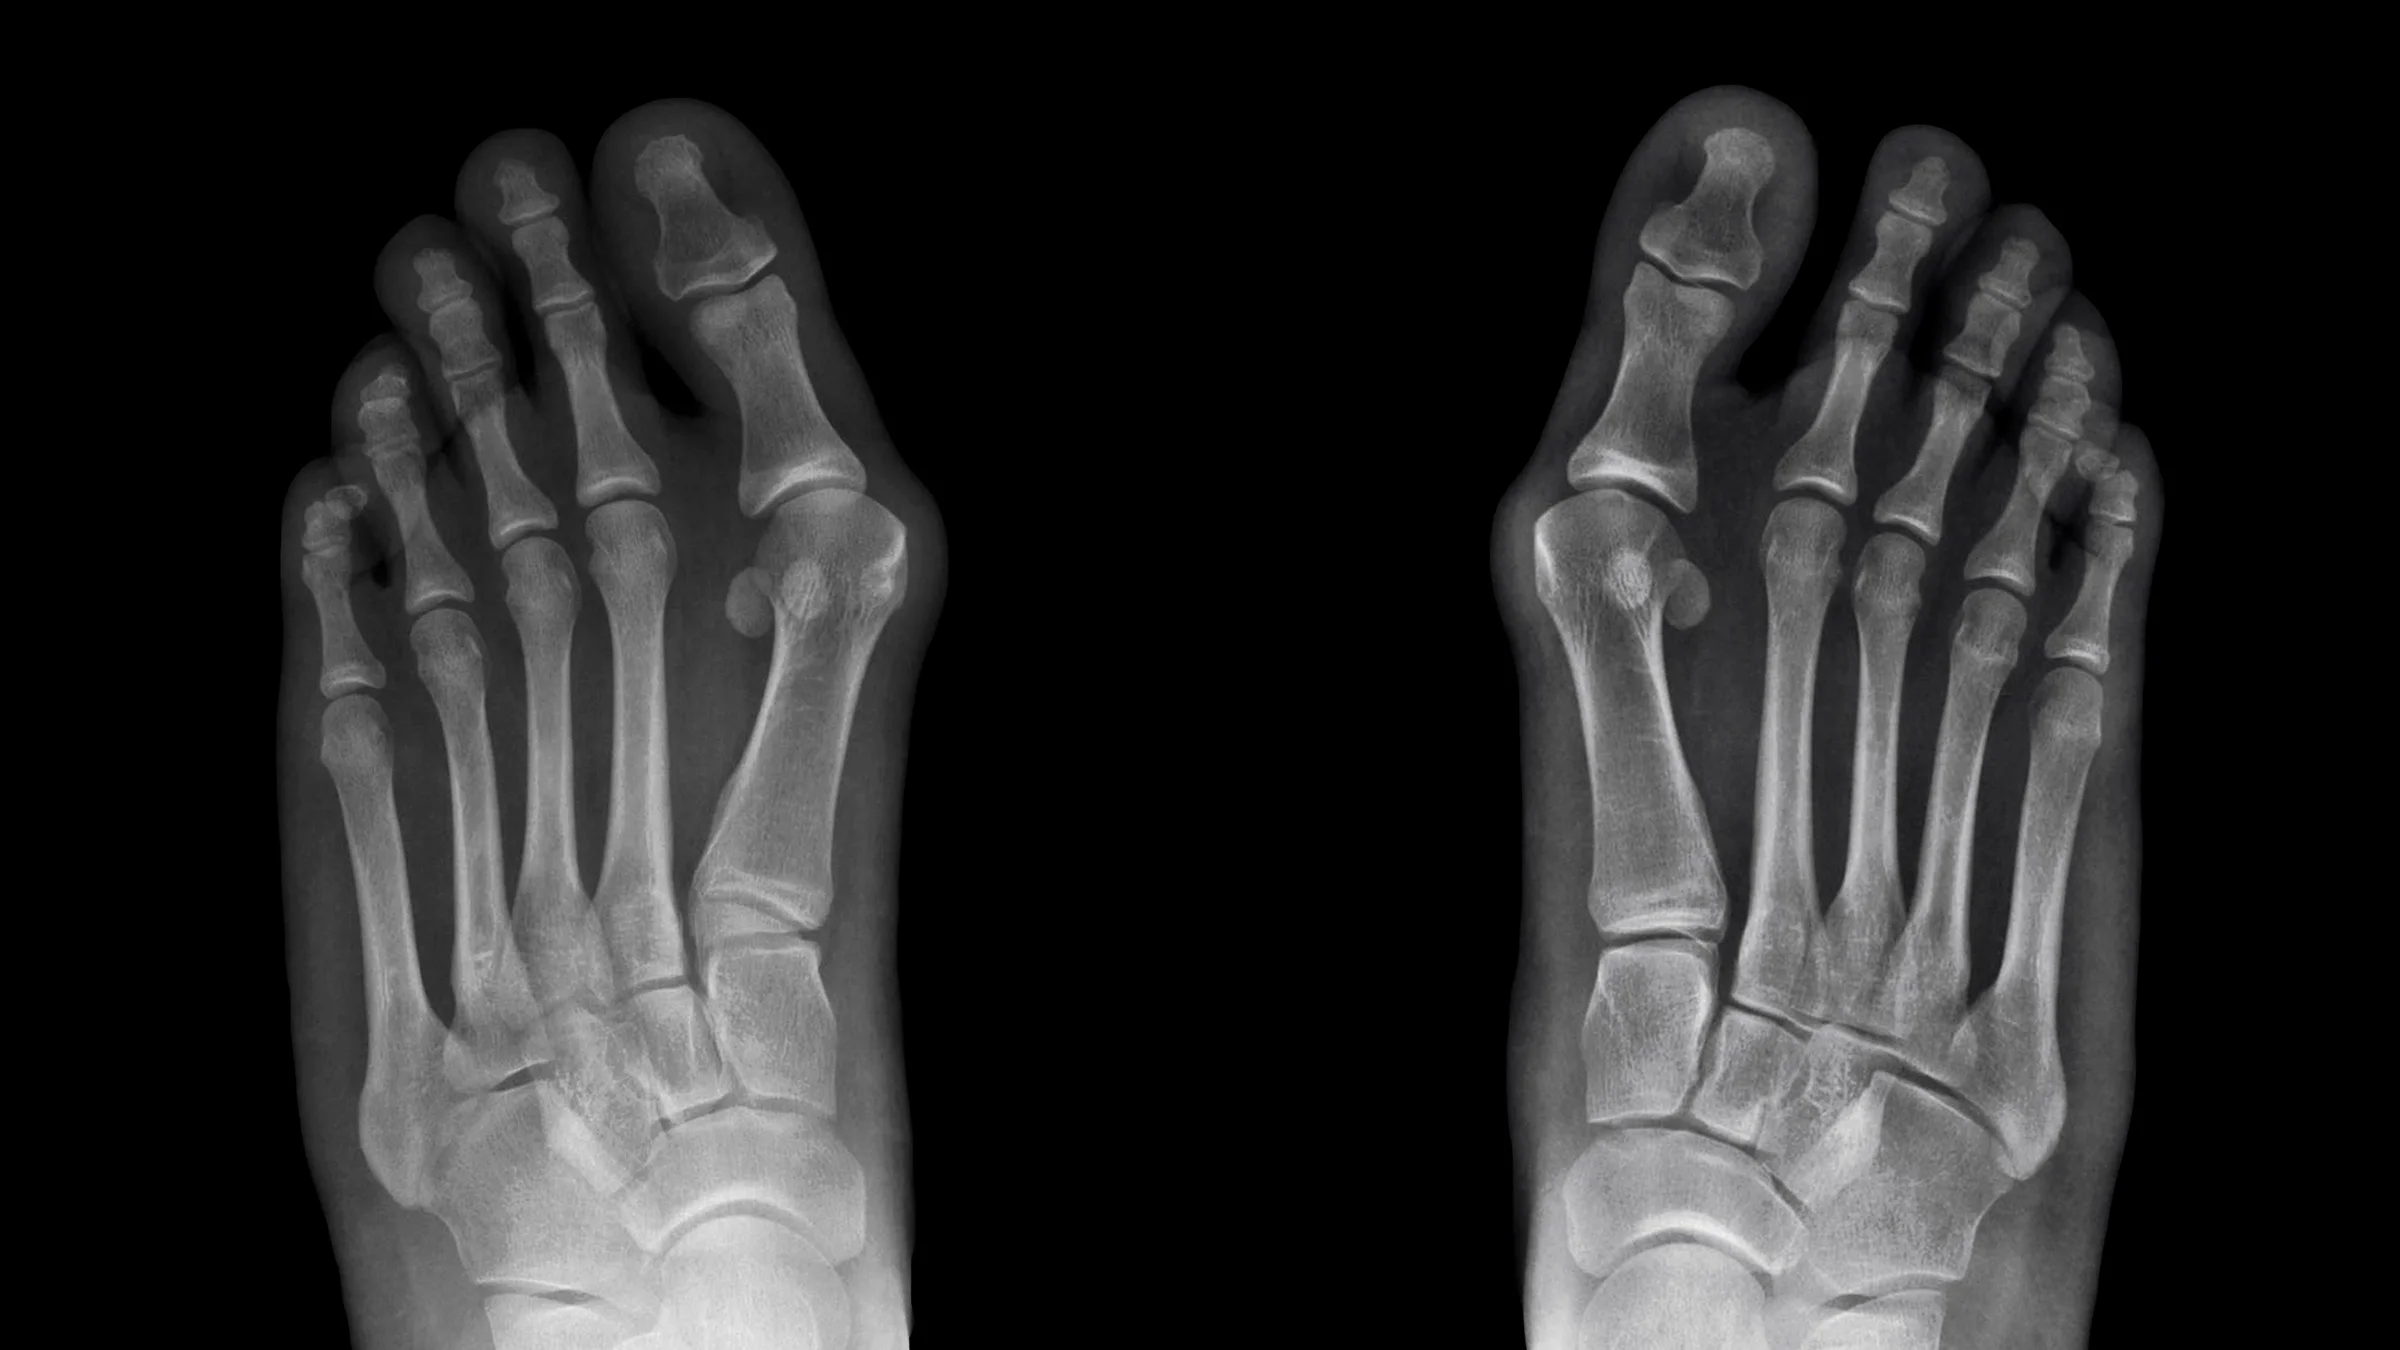

Bunions are bony knobs on the foot that appear at the joint at the base of the big toe. Left untreated, a bunion (hallux valgus) can become painful and may impair your ability to walk normally.

People with bunions often choose to undergo surgery to correct the physical deformity and related pain. There are several types of bunion surgery. And they all typically involve repositioning the misaligned bones, repairing nearby tendons and ligaments, and possibly fusing the joint.

Bunion correction surgery is one the most common forefoot surgeries, with more than 350,000 procedures performed annually in the U.S.